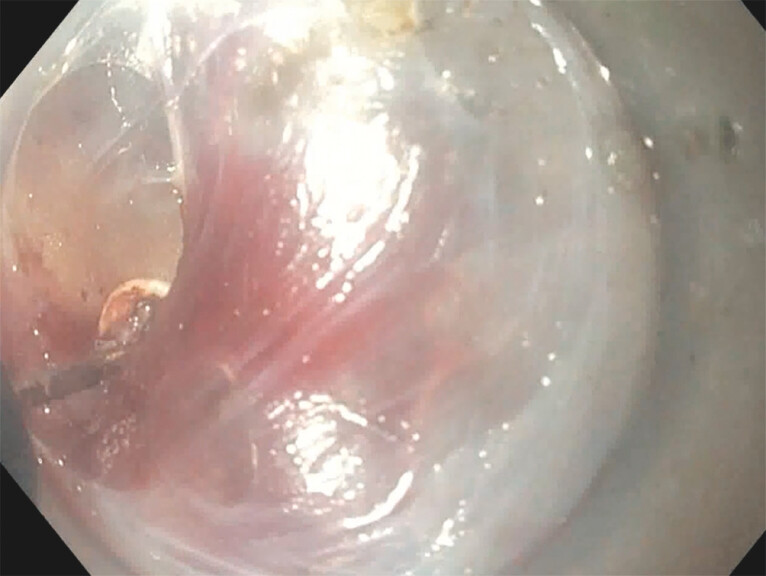

Background and study aims: Gastroesophageal reflux (GERD) can occur in a significant number of achalasia patients undergoing post-peroral endoscopic myotomy (POEM). POEM with endoscopic fundoplication (POEM-F) is a new endoscopic technique to treat post- POEM GERD. We conducted a multicenter cohort study to compare outcomes between POEM and POEM-F.

Results: Sixty-four patients were included: 31 patients underwent POEM-F (mean age 51, 48% male), whereas 33 patients POEM (mean age 56, 58% male). Technical success was 100% in both groups. POEM-F patients achieved reduction/cessation in proton pump inhibitor use in 25 of 31 patients (80%); POEM patients in eight of 33 (24%) ( P ≤ 0.00001). Percent time with pH < 4 was significantly lower in the POEM-F group (2.75 +/- 2.53 vs 9.3 +/- 3.6 min, P ≤ 0.0001). Post-procedure DeMeester scores were lower (< 14.7) in POEM-F (mean 9.6) than POEM (mean 15.8) ( P ≤ 0.0011). There were three mucosal injuries in the POEM-F group and four in the POEM group. Hospital stay duration and procedure time did not differ between groups. In the POEM group, four patients required Dor fundoplication. No repeat interventions were recommended for the POEM- F group at 6-month follow-up.

Conclusions: POEM-F achieves statistically significant improvement in post- POEM GERD compared with POEM alone.